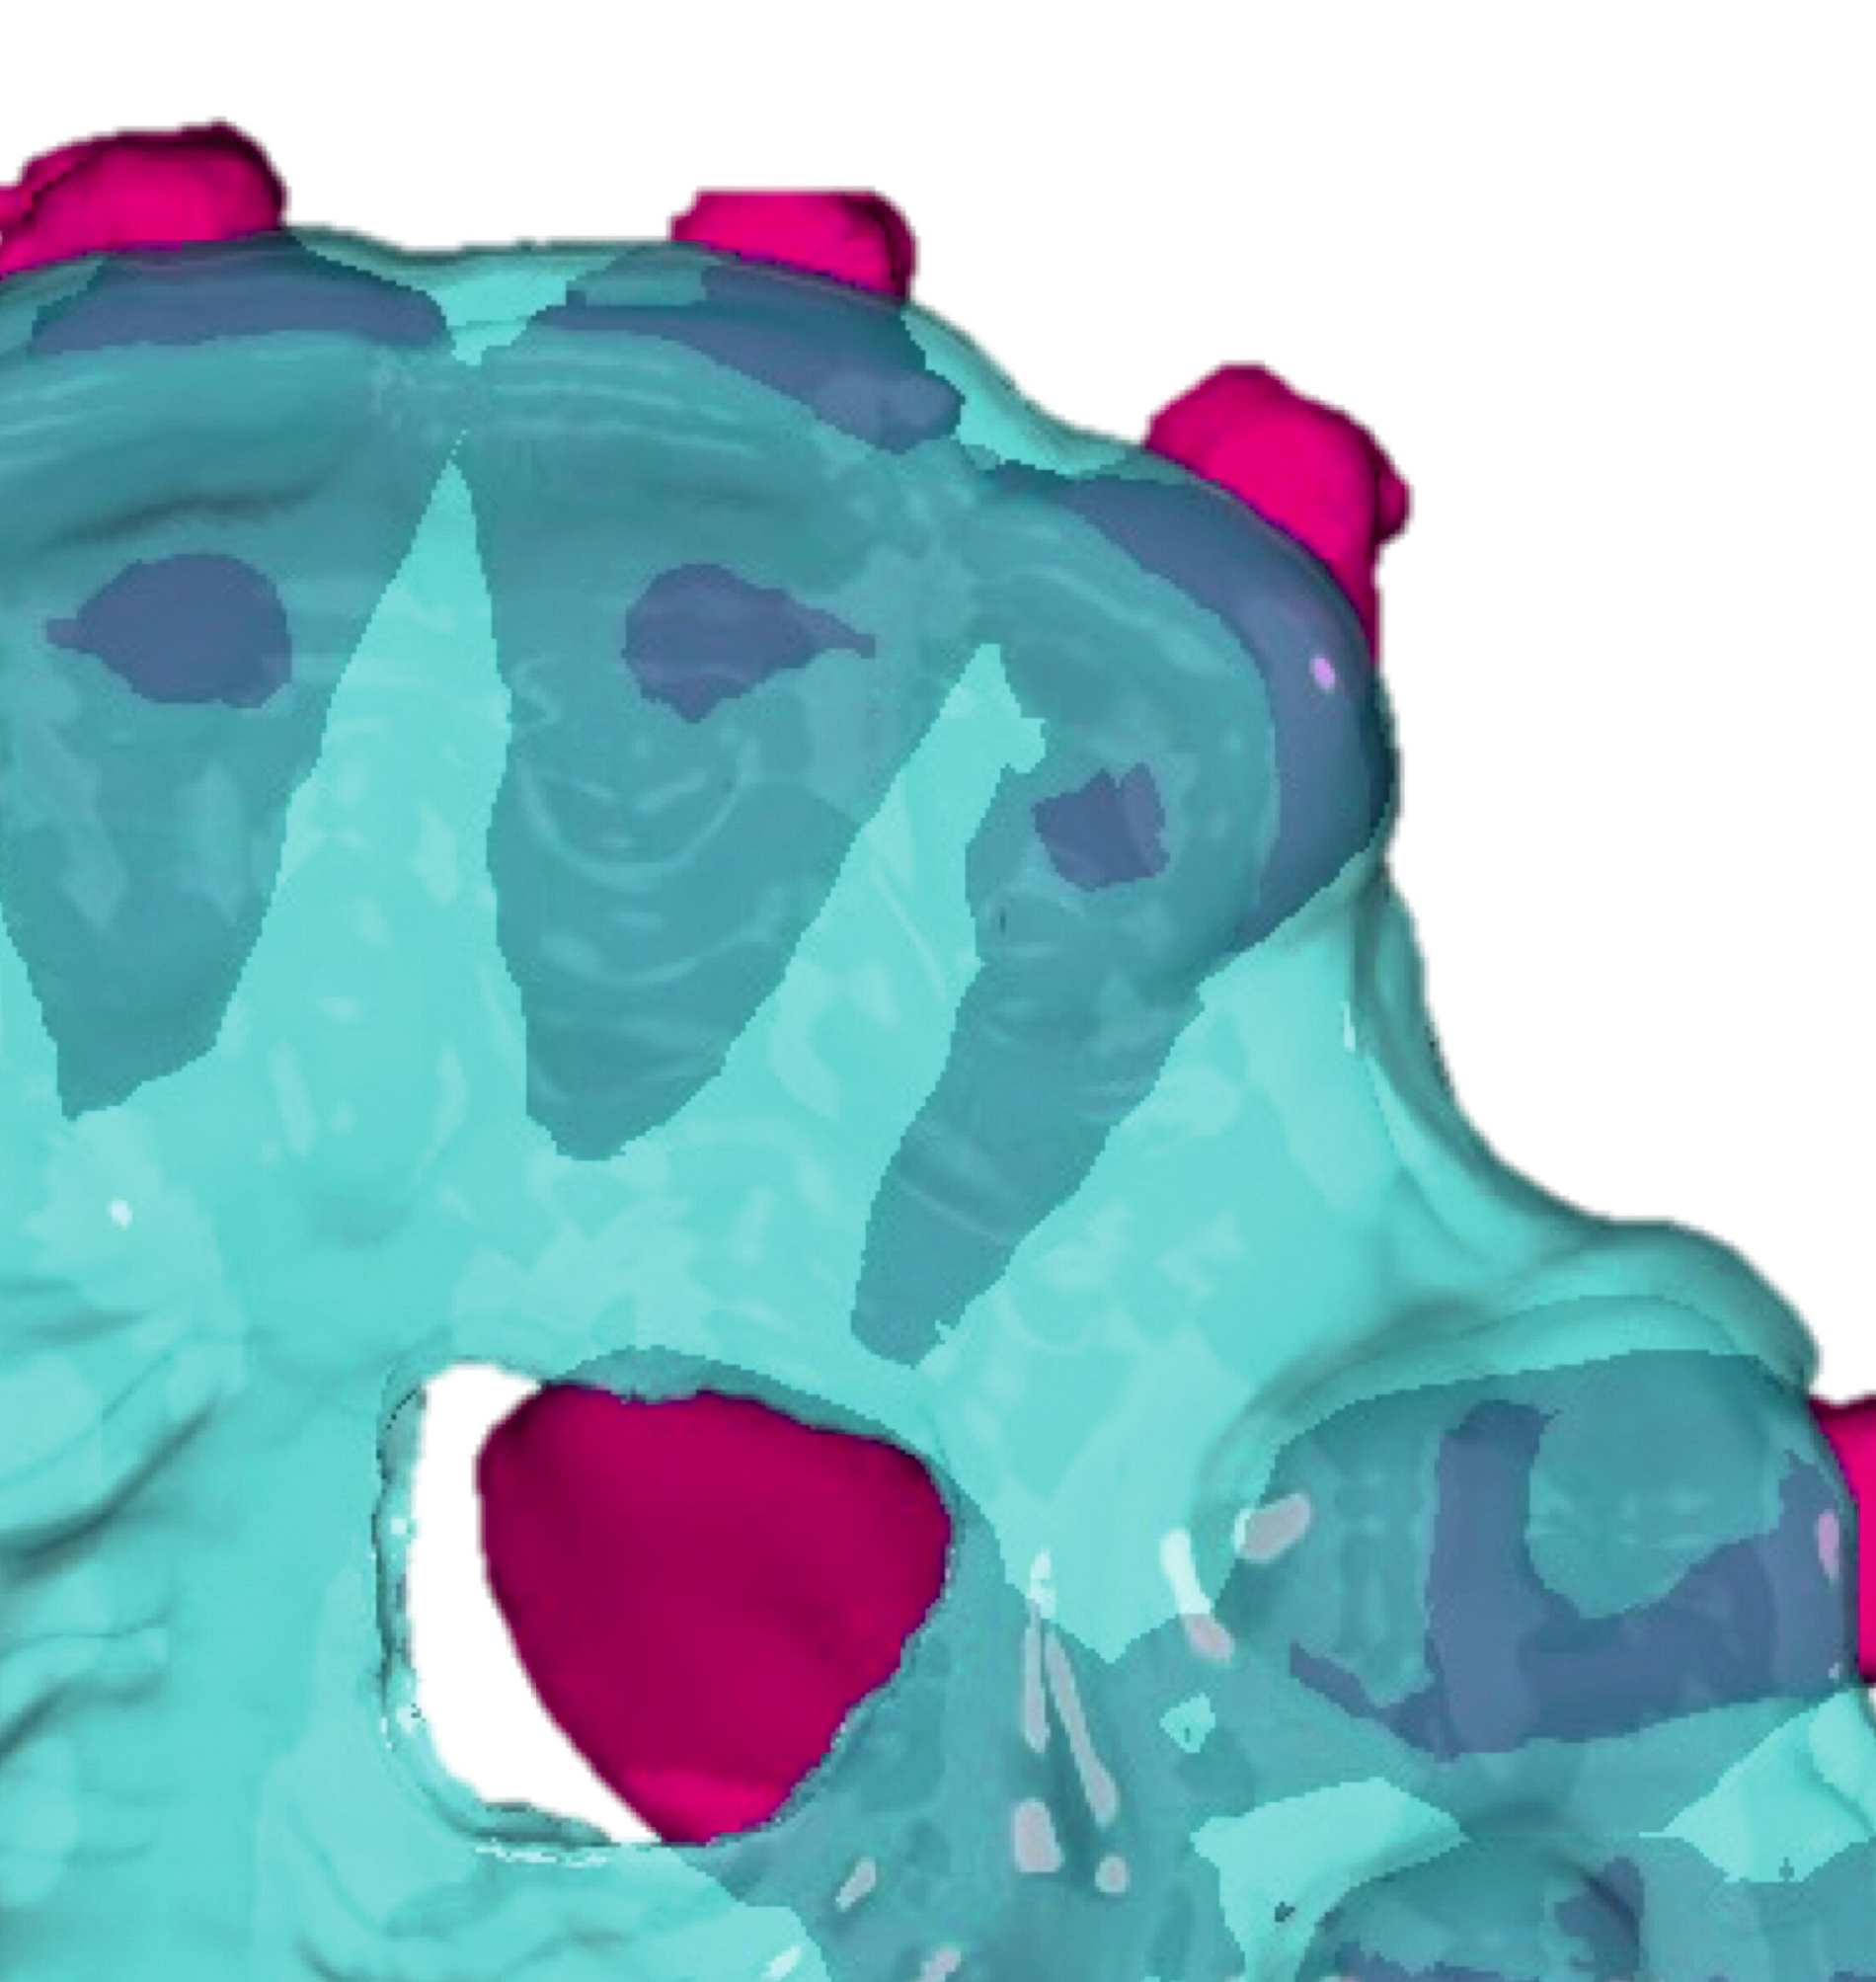

Als Alternative zu Alignern können auch Brackets mittlerweile im 3-D-Druckverfahren hergestellt werden [Sha et al., 2018; Sha et al., 2019; Bauer et al., 2023] (Abbildungen 2a und 2b). Neben der Nutzung des Angebots kommerzieller Anbieter (beispielsweise Lightforce Company) besteht dabei die Möglichkeit der Herstellung im praxisinternen 3-D-Drucker. Zum Einsatz eignen sich unter anderem Keramik-gefüllte 3-D-Druckkunststoffe der Biokompatibilitätsklasse IIa, die für einen langfristigen intraoralen Einsatz zertifiziert sind (zum Beispiel Permanent Crown Resin, Formlabs) [Papageorgiou et al., 2022; Bauer et al., 2023; Hodecker et al., 2023; Panayi, 2023].

Die Vorteile bestehen vordergründig in einem individualisierten Design, das die jeweiligen Therapieanforderungen berücksichtigt. Bisherige Forschungsarbeiten zeigen eine mit konventionellen Metallbrackets vergleichbare Präzision [Bauer et al., 2023], so dass eine korrekte Übertragung kieferorthopädischer Kräfte gewährleistet ist. Der Haftverbund zeigt sich gegenüber konventionellen Metallbrackets noch etwas schwächer [Hodecker et al., 2023]. Durch weitere Entwicklungen im Bereich der Bracketbasis dürfte diese Limitation jedoch adressiert werden können.